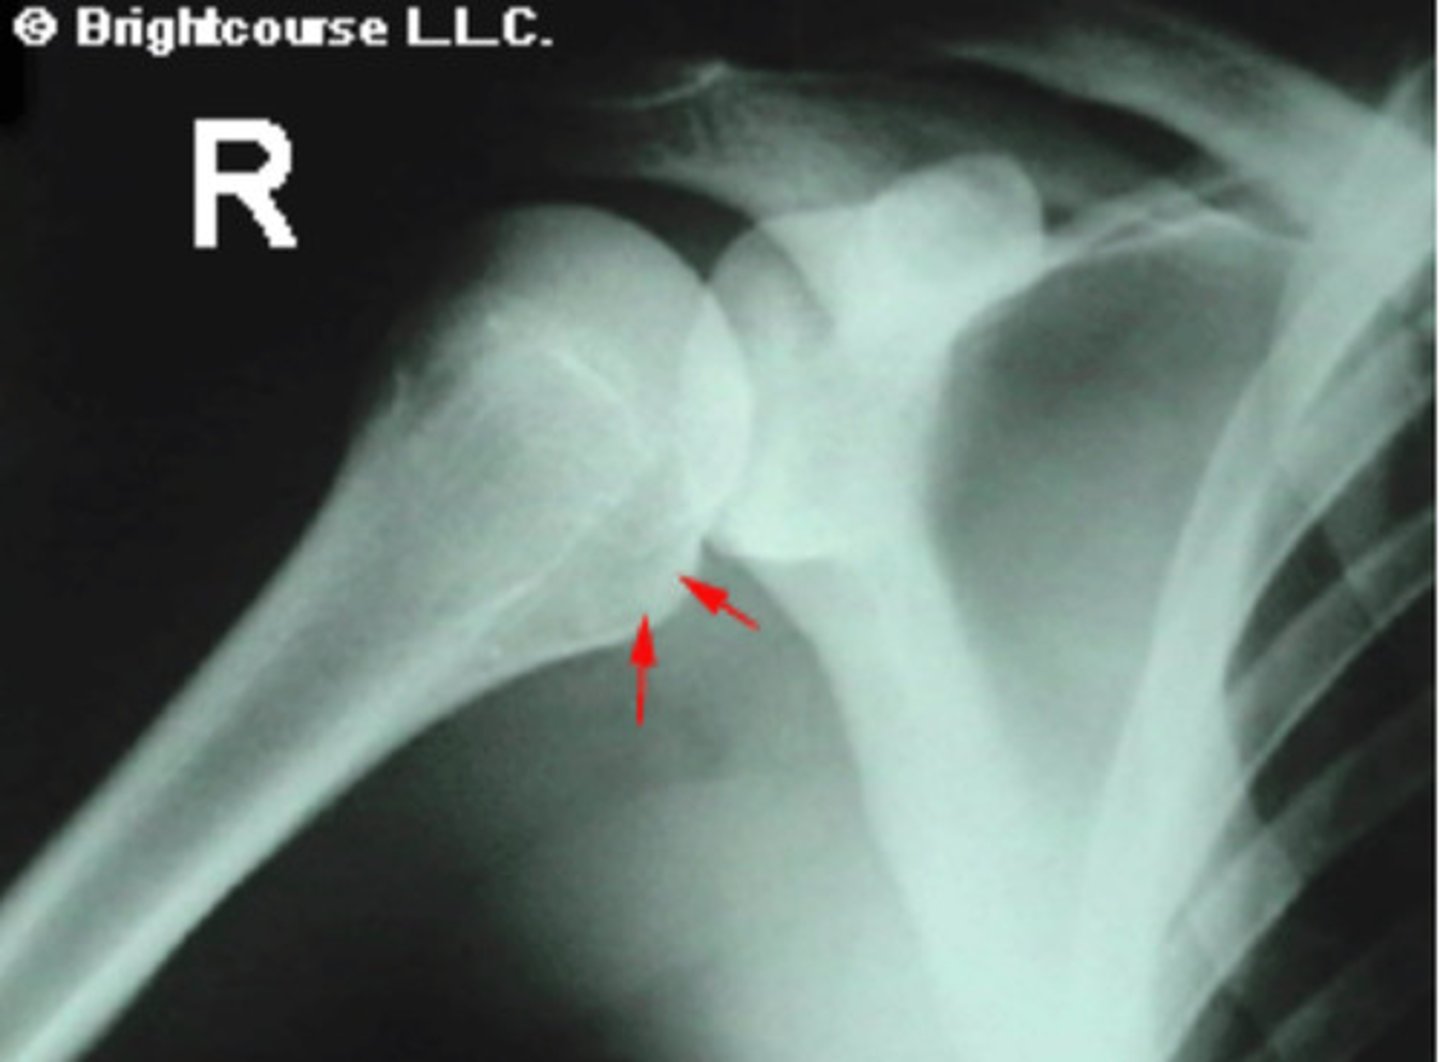

Lesser tubercle

What is being pointed out by the arrows in the image?